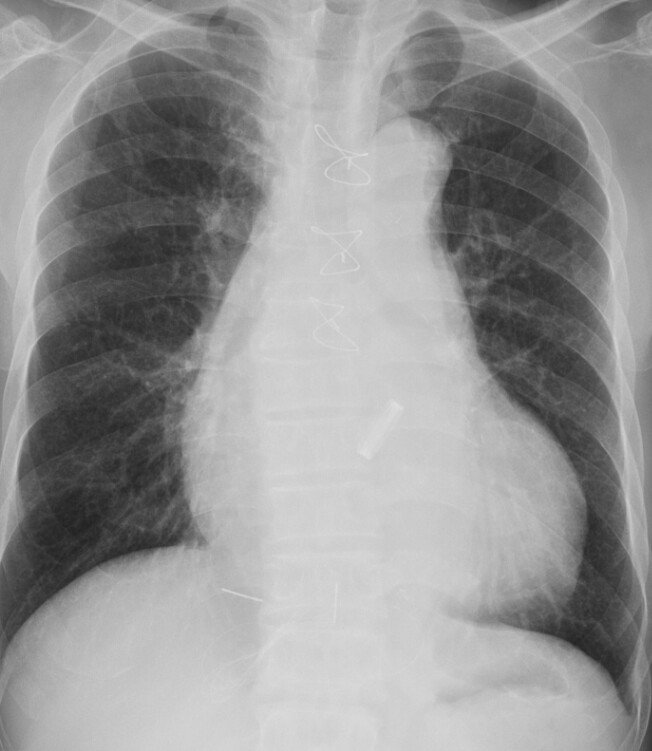

好奇怪,怎么回事,昨天晚上一个人在家睡觉,起床后,周围全都是血,我床上好多,我家小狗一直在看我,不出声,起来后好奇怪。吓死我了,那里的血,检查自己,没有伤口,上午去一趟医院全面检查没问题,还有我家都锁这门,没有人进来,在说我家住9楼,我是男的,这怎么回事,帮帮我,起来就是胸口特别疼,但是没有刀痕问题  这个是胸部的

这不是一个人的片子吧。。第二张现实你肺气肿伴重度心脏肥大,赶紧住院吧,就你这情况分分钟心衰猝死